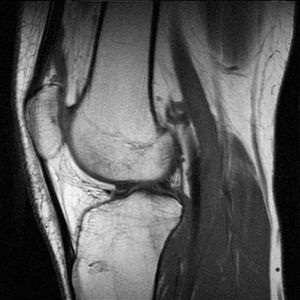

للرنين المغناطيسي أستخدمات تشخيصية متعددة لأنه قادر و بدقة عالية على تصوير الأنسجة الداخلية دون التركيز على العظام مما يساعد على تشخيص الأورام خبيثة أو حميدة التي تنبع من الأنسجة

T1-weighted MRI

T2-weighted MRI